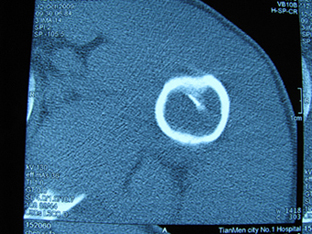

标题: X6404B:肱骨骨质破坏(CT片) [打印本页]

标题: X6404B:肱骨骨质破坏(CT片)

男,50岁,左肩部轻微疼痛,活动不便5个月就诊,近十天加重,无红肿热,间断理疗治疗无好转,既往5个月前左肩轻微拉伤史

骨巨?动脉瘤样骨囊肿?

内生软骨瘤。

内生软骨瘤。

内生软骨瘤?-----------

年纪大了,先要排除转移瘤。

髓腔内软组织肿块并斑片状钙化,考虑高分化软骨肉瘤可能性大。

考虑骨巨或动脉瘤样骨囊肿。

内生软骨瘤可能性大,期待结果。

孤立性骨囊肿。

内生软骨瘤可能性大

其内可见钙化,考虑软骨源性肿瘤,内生软骨瘤可能

但由于年龄较大,恶性软骨肉瘤待排

肱骨头内巨大软组织肿块并斑片状钙化,内生软骨瘤?骨巨细胞瘤?软骨粘液样纤维瘤?期待结果!

髓腔内软组织肿块并斑片状钙化,考虑高分化软骨肉瘤可能性大。

内生软骨瘤可能性大

肱骨头内巨大软组织肿块并斑片状钙化,内生软骨瘤?骨巨细胞瘤?软骨粘液样纤维瘤?期待结果

考虑内生软骨瘤?骨巨细胞瘤?

内生软骨瘤?骨巨细胞瘤?

先要排除转移瘤。